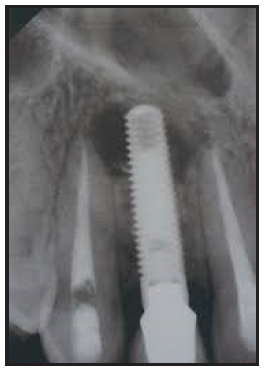

The purpose of the intraoral periapical examination is to obtain a view of the entire tooth and its surrounding structures, as in Figure 1. Two exposure techniques may be employed for periapical radiography: the paralleling technique and the bisecting angle technique. The paralleling technique is the preferred method. This technique provides less image distortion and reduces excess radiation to the patient. The paralleling technique should always be attempted before other techniques. The bisecting technique can be employed for patients unable to accommodate the positioning of the paralleling technique. Candidates may include those with low palatal vaults and children. Disadvantages to the bisecting technique include image distortion and excess radiation due to increased angulations involving the eye and thyroid glands. Regardless of the technique, however, the rules of radiography referred to earlier must be followed.

Figure 1 – Periapical Image

Figure 1